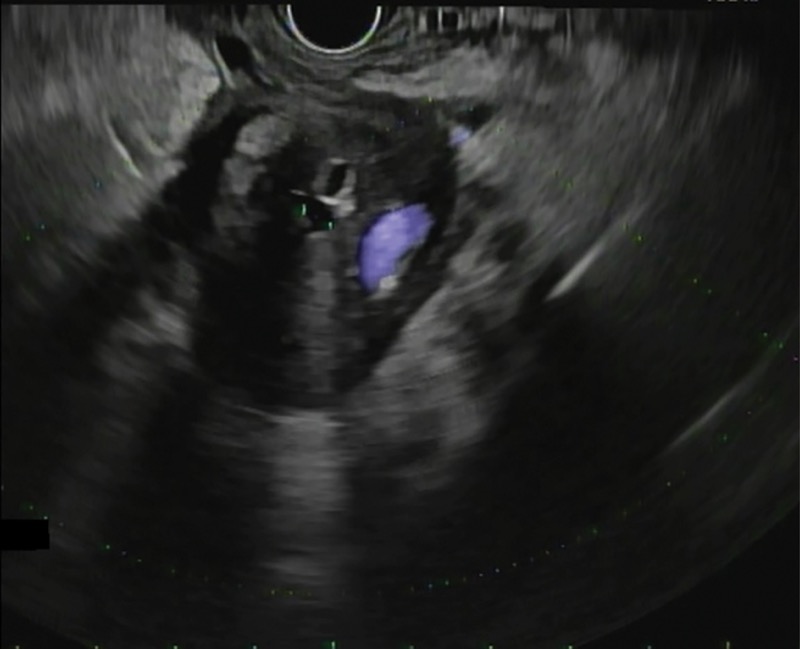

In the past, at the time of ERCP, it was recommended that bile be collected from the duodenum or bile duct after gallbladder stimulation with cholecystokinin or by direct cannulation of the gallbladder.36,37 Today, however, ERCP rarely is performed specifically for bile crystal analysis, given the risk for post-ERCP pancreatitis and the high sensitivity of EUS in detecting biliary sludge and microlithiasis (Figures 2 and 3A). Furthermore, TUS technology also has advanced significantly, with improved detection rates.

In a large meta-analysis, EUS was found to have a significant benefit in detecting occult biliary disease compared with MRCP (Figure 3B) in IAP.29 Ardengh et al found gallbladder microlithiasis in 27 of 36 patients with IAP using EUS (75%).38 When compared with the final surgical resection specimen, the sensitivity and specificity for EUS identification of gallbladder microlithiasis were 92.6% and 56%, respectively. The overall EUS accuracy in this study was 83.2%.